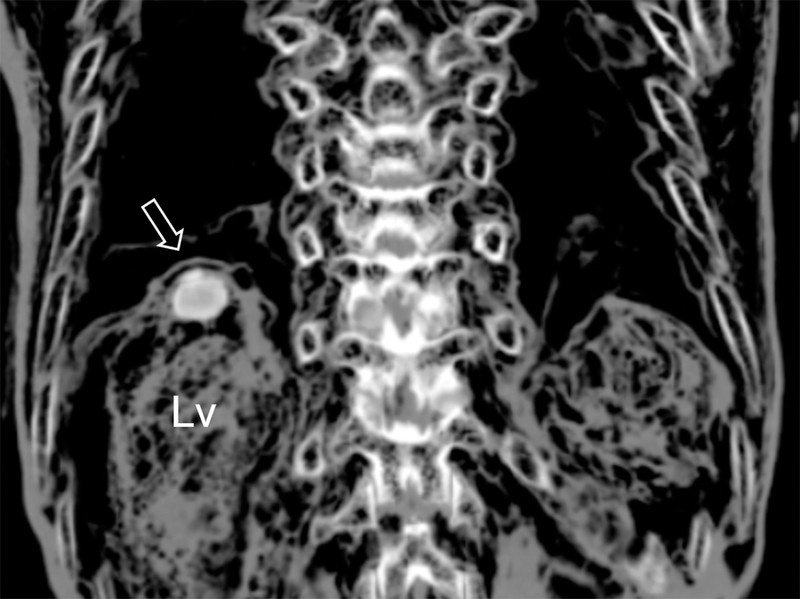

Компьютерная томография обнаружила в печени 375-летней мумии мужчины странное образование. Детальный анализ показал, что в тканях присутствуют яйца трематод вида Paragonimus westermani - паразитических плоских червей.

Мумия была найдена в Китае в 2014 году. Мужчина умер в 1642 году, ему было около 63 лет. Тело прекрасно сохранилось.